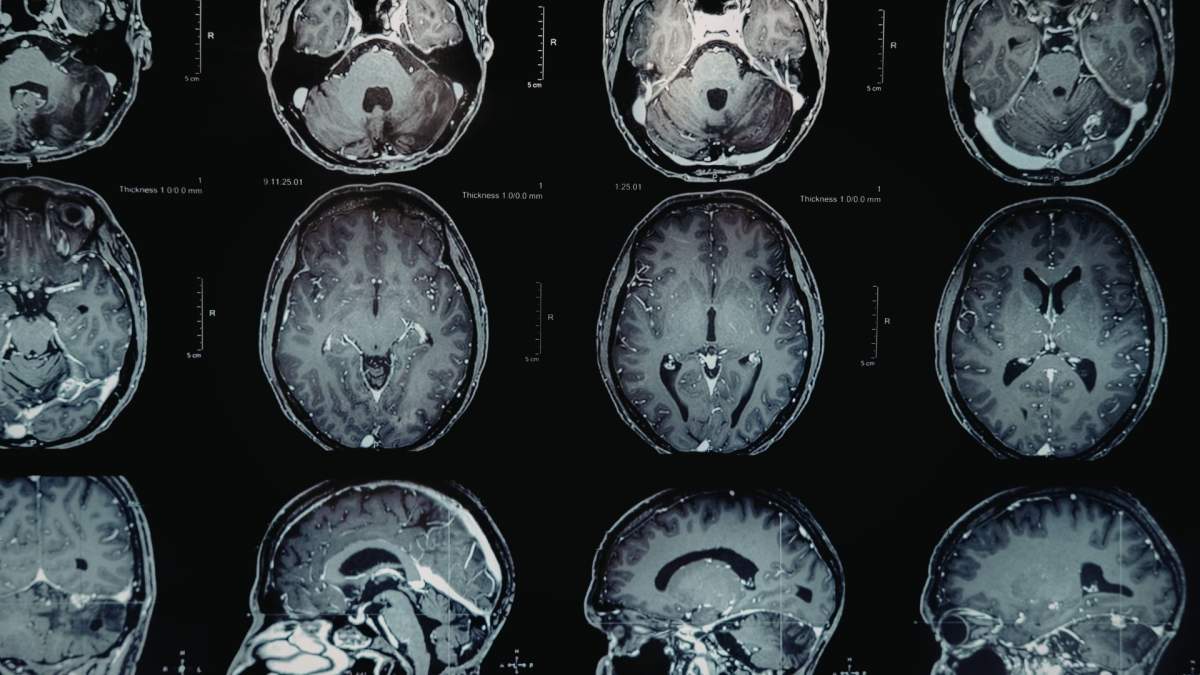

Gilbert fue diagnosticado con cáncer suprarrenal en etapa 4 en 2021, pero su diagnóstico cambió a principios de este año cuando los médicos descubrieron tres tumores cerebrales.

Después de someterse a escáneres, los médicos le dijeron al rockero que tenía tres tumores cerebrales, uno tan grande como una nuez.

“El 20 de febrero, di un concierto en Nashville y tenía dificultades para controlar los movimientos de mi mano izquierda. Mi pierna izquierda se debilitaba cada día más, y comencé a tropezar y caerme a veces. El 23, me llevaron a la sala de emergencias, donde una tomografía computarizada mostró que habían aparecido 3 nuevos tumores en mi cerebro”, compartió junto a una foto desde su cama de hospital. El 27 de febrero me operaron del cerebro y desde entonces me estoy recuperando en el hospital. Recuperé la movilidad de mi mano izquierda inmediatamente 🙏🏻.